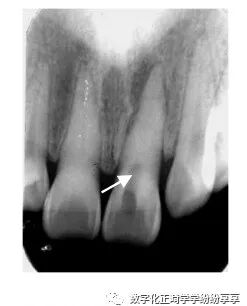

牙内陷

曲面断层片怎么看正畸【曲面断层片(全景片)】如何解读和查看:牙周?牙体?牙髓?关节?_https://www.jmylbn.com_新闻资讯_第17张

①右上 2 畸形舌侧尖(伴阻生牙);②左上 2 畸形舌侧窝;③右上 2 牙中牙

融合牙

曲面断层片怎么看正畸【曲面断层片(全景片)】如何解读和查看:牙周?牙体?牙髓?关节?_https://www.jmylbn.com_新闻资讯_第18张

分别为右下 1、2 的完全性融合和不完全性(牙冠)融合